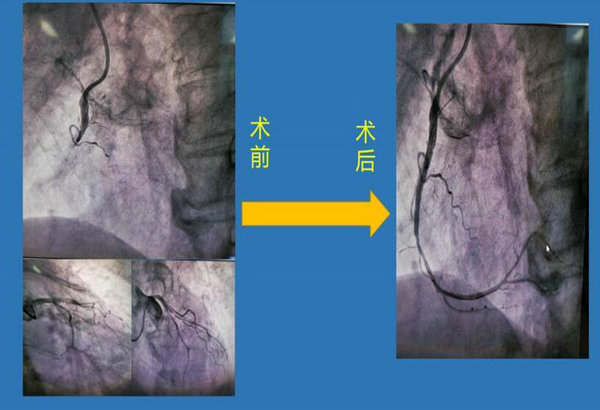

术中见LAD中段95%狭窄,RCA近中段100%完全闭塞,开通血管并植入支架一枚,在曹春明医生、秦川宇医生及介入科医护的共同努力下,将患者生命从死神手中快速夺回,患者来诊到手术完成仅用37分钟,好在抢救及时,王大爷恢复了正常心脏供血,目前恢复良好。

心血管内科七病区治疗团队为患者行冠脉造影术

术前术后对比图